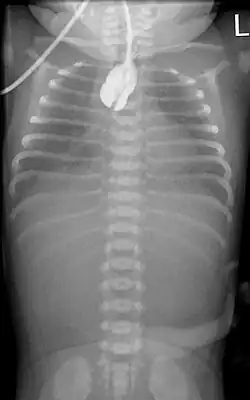

Ösophagusatresie Typ 3b nach Vogt: Kontrastmittel im oberen Blindsack. Reichlich Luft im Magen-Darm-Trakt.

Zur Diagnosefindung wird die Speiseröhre sondiert. Ein federnder Stopp ist hinweisend. Eine Röntgenaufnahme des Brustkorbes zeigt die Luftfüllung des oberen Blindsackes (sog. Medaillonzeichen), und gegebenenfalls eine Luftfüllung des Darmes als Hinweis auf eine untere Fistel. Nur in Ausnahmefällen wird zusätzlich wasserlösliches Kontrastmittel gegeben.